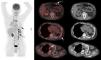

Presentamos el caso de un paciente de 54 años, con antecedentes de pleuroneumectomía, frenicectomía y pericardiectomía por mesotelioma pleural izquierdo con esplenectomía metastásica a los 2 años. Tras un periodo libre de enfermedad de 14 años, se objetivaron por TC pequeñas adenopatías mediastínicas y un nódulo sólido de contornos polilobulados en la vaina de los músculos rectos del abdomen. Mediante PET/TC de extensión con 18FDG se observaron lesiones hipermetabólicas (fig. 1, flechas), linfáticas, mediastínicas y en planos musculares del serrato mayor izquierdo, parrilla costal y recto anterior izquierdo del abdomen (fig. 1, asterisco), donde se alcanza un SUV máximo de 5,7. Mediante biopsia muscular abdominal se confirmó la infiltración por mesotelioma epitelial, iniciándose tratamiento con esquema cisplatino-pemetrexed.

Imagen MIP (proyección de máxima intensidad) y cortes axiales del estudio PET/TC con 18FDG que muestra depósitos hipermetabólicos del trazador de localización linfática mediastínica y locorregional en serrato mayor izquierdo, parrilla costal y recto anterior izquierdo del abdomen (flechas), así como cambios secundarios a los antecedentes quirúrgicos en el hemitórax izquierdo. La lesión con mayor tasa metabólica es la localizada en el recto anterior izquierdo del abdomen (asterisco), con SUVmáx 5,7.